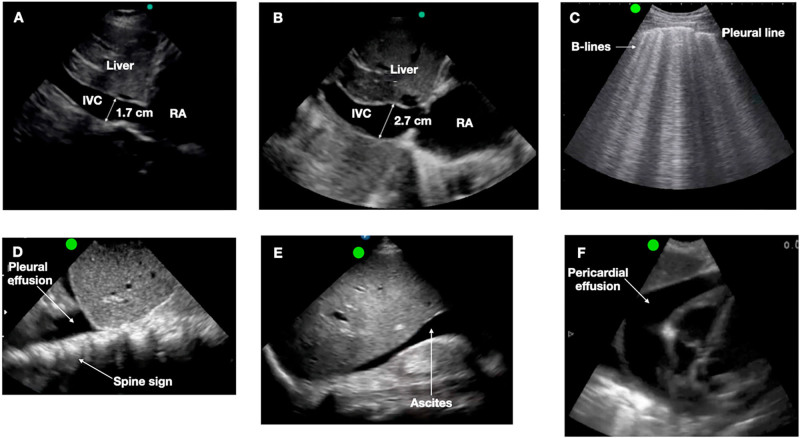

Abstract Image